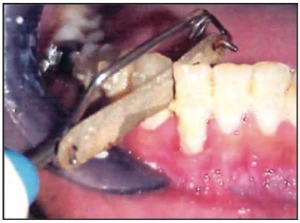

Mũi khoan

Mũi khoan thẳng và thuôn có thể được sử dụng để mài kẽ. Chúng thường để lại sẹo sâu trên men răng và vì vậy cần dũa lại bằng dải kim loại mài kẽ để làm bóng vùng này.

Hình 1D. Mũi khoan kim cương mịn mảnh